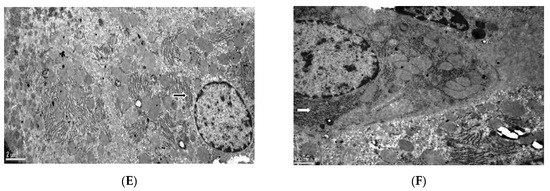

3.5. Histopathological Examination